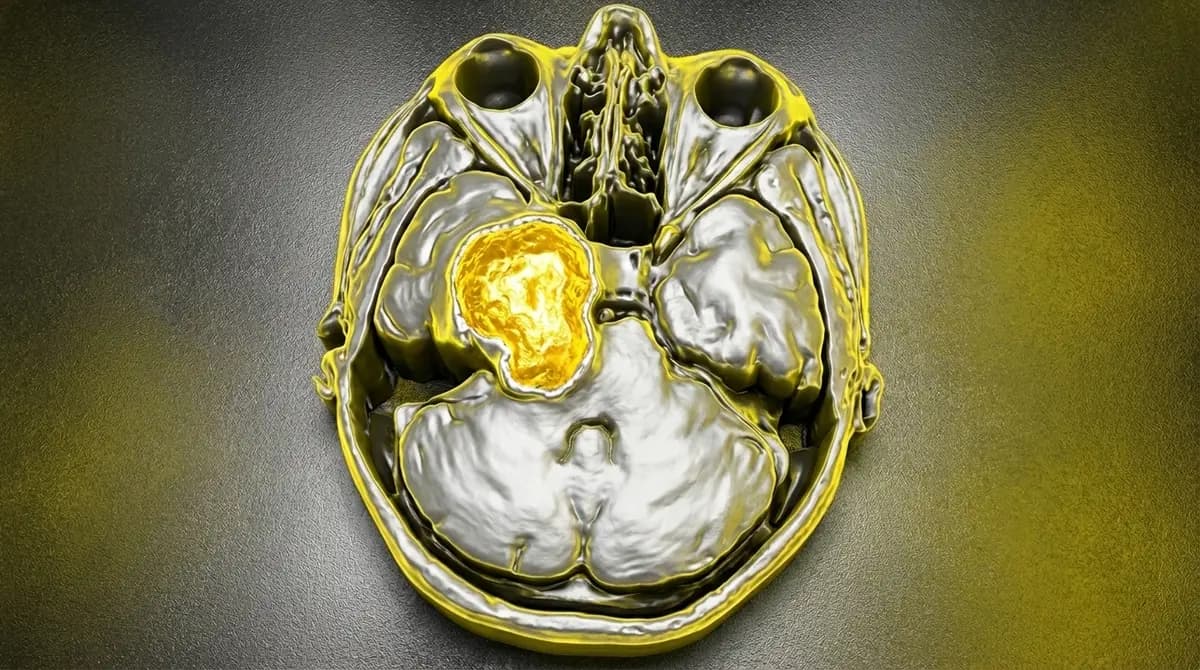

Tumor benigno (Grau I) que nasce das células de Schwann do nervo trigêmeo (V par craniano). Pode crescer na fossa média (perto da têmpora) ou no ângulo ponto-cerebelar (perto do ouvido). Diferente da neuralgia do trigêmeo clássica, aqui há perda de sensibilidade e possível fraqueza muscular.

- 📊 RM com contraste (diagnóstico diferencial com meningioma)